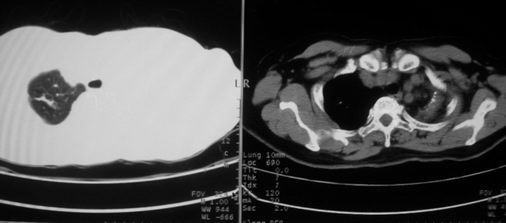

以下是引用李衡钧在2008-7-24 14:24:00的发言:[br]左侧胸廓变小,左肺上叶见大面积致密阴影,其内有空洞及不规则钙化。上纵隔略向左移位,上肺胸膜增厚。左肺门及纵隔淋巴结增大。右肺见散在的致密结节影。[br]印象:继发性肺结核。